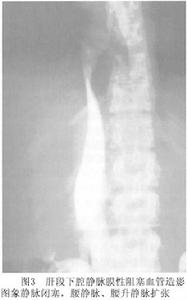

3.MRI檢查MRI具有多平面、血管流空效應、無創的特點,可顯示肝靜脈下腔靜脈走行,肝靜脈下腔靜脈回流受阻是先天性異常或繼發於腫瘤、血栓或其他因素,還可發現腹水、側支循環建立等徵象。不足是有時鑑別慢血流與血栓困難,不能判斷血流方向。

(1)肝臟腫大,肝臟信號改變,T2加權圖像上尾狀葉信號強度低於其他組織,是由於解剖上尾狀葉的血流直接引流入下腔靜脈,當肝靜脈回流受阻,尾狀葉一般不受累或受累較輕。

(2)肝靜脈、下腔靜脈形態異常,肝靜脈狹窄或閉塞,肝靜脈與下腔靜脈不連線,肝段下腔靜脈明顯狹窄或阻塞,可顯示下腔靜脈隔膜和阻塞段,阻塞端以下下腔靜脈擴張血流速度減慢可呈強弱不等信號。肝靜脈和下腔靜脈血栓形成,呈軟組織高信號,矢狀面冠狀面成像能顯示其範圍肝內側支血管形成,呈“逗點狀”或“蜘蛛網”狀走行紊亂。

(3)伴發腹水,T1加權圖像上肝周圍低信號T2加權圖像上呈高信號。

(4)肝臟、椎旁間隙、腹壁靜脈呈代償性擴張低信號,奇靜脈擴張。

(5)可清晰顯示下腔靜脈和右心房的解剖結構為本病診斷提供重要的術前信息(圖2)。